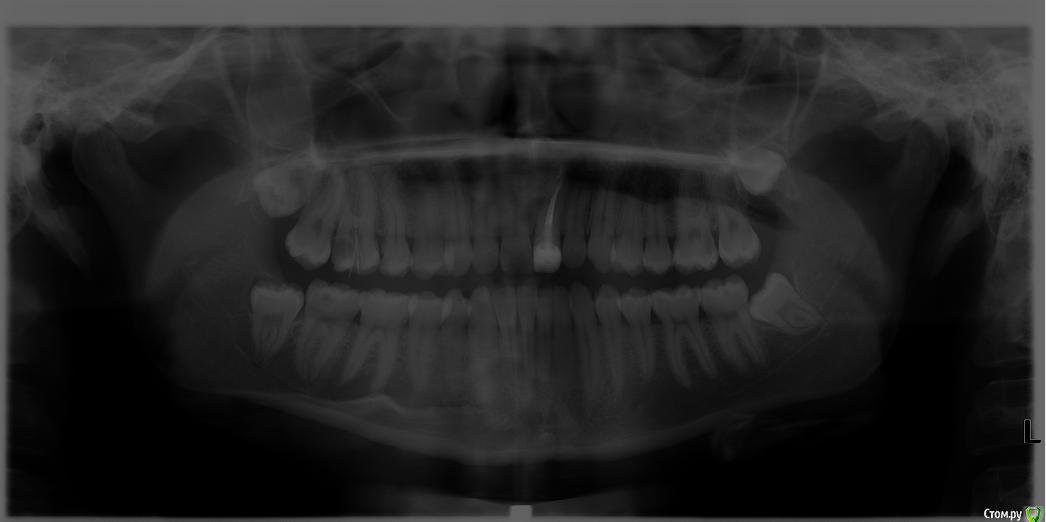

Irusick Опубликовано 21 июля, 2017 Поделиться Опубликовано 21 июля, 2017 страшно писать, после всего крутого, что я прочла до этого в теме... но закидайте меня камнями. Помогите увидеть очертания небного корня 1.6, снимок оставляет желать лучшего, но работаем с тем, что есть( 1 Ссылка на комментарий

parallax Опубликовано 21 июля, 2017 Поделиться Опубликовано 21 июля, 2017 Так вроде инструмент в нёбном канале? И вообще, уберите кариес дистально, сделайте билдап. И пошлите паца на нормальный прицельный снимок, желательно с коффером. 2 Ссылка на комментарий

Irusick Опубликовано 21 июля, 2017 Поделиться Опубликовано 21 июля, 2017 Так вроде инструмент в нёбном канале? И вообще, уберите кариес дистально, сделайте билдап. И пошлите паца на нормальный прицельный снимок, желательно с коффером.. Нет прицельного рентгена в клинике. У меня часто бывает, что из-за страха перфораций либо свод до конца не уберу, либо испугает объемная пульпа в небном как сейчас, видела Ее как губку, а на рентгене контуров корня не вижу,побоялась, что уже наделала дел, в следующий приём доведу до ума. Спасибо! Ссылка на комментарий

parallax Опубликовано 21 июля, 2017 Поделиться Опубликовано 21 июля, 2017 У Вас дистальный щёчный не найден. И ОПТГ при эндодонтии - это не айс. Ещё пара таких снимков и пациент начнёт блевать от передоза радиации. 2 Ссылка на комментарий

Irusick Опубликовано 21 июля, 2017 Поделиться Опубликовано 21 июля, 2017 Дистальный и медиальный я нашла, вставила гутту как раз для того, чтобы прояснить ситуацию с небным. А насчёт рентгена, я понимаю, потому что сама четких границ не вижу и опыта мало, но в моей ситуации - хозяин-барин, такие условия работы. И отправить куда-то по близости за прицельным нет возможности Ссылка на комментарий